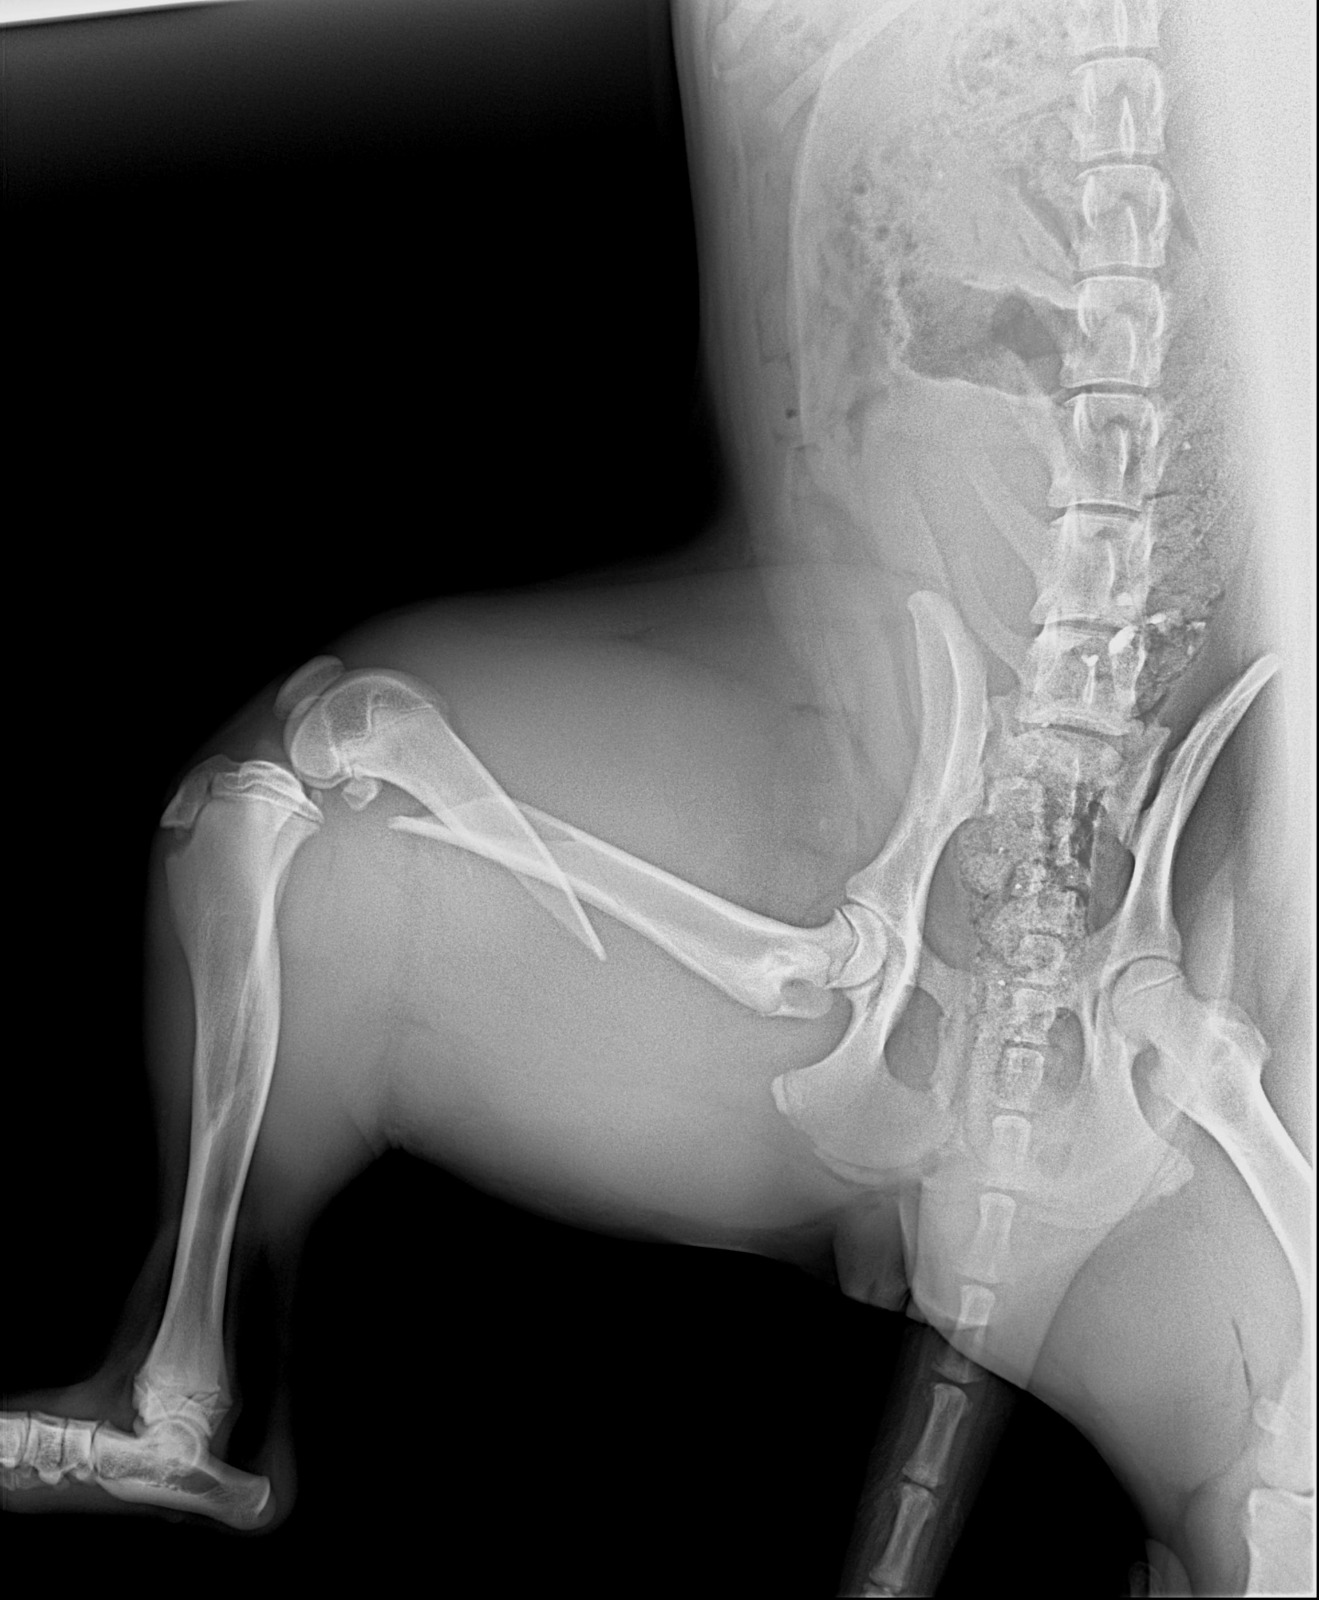

These dogs are in south lebanon rescued from war zone after being left behind. The one to the left was hit by a car and have a broken hip as shows frkm x rays and needs an urgent operation. It costs 650 usd as per the screenshot of chat with the vet. Please your help us needed. We can not afford as we are not working currently.